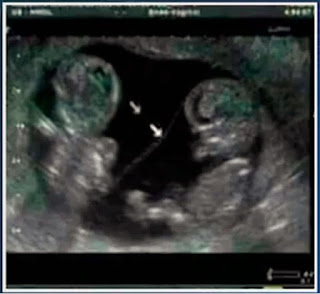

ultrassonografia da gravidez dela foi feita no dia 3 de junho, quando

ela estava com 37 semanas. O exame mostrado por Cleidiane confirma que

ela estava grávida de gêmeos, e até descreve os dois fetos. A dona de